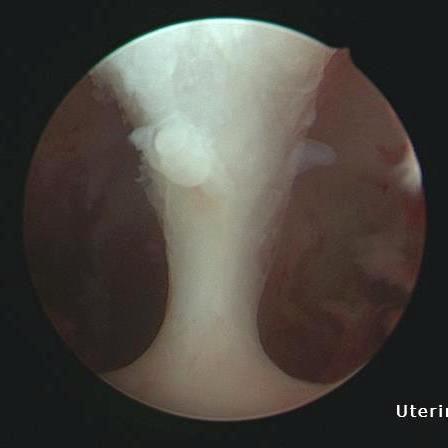

圖:利用診斷性子宮鏡,李佩蓁醫師發現賴女士的子宮腔內有明顯間隔,確診為間隔子宮。

賴女士患有多囊性卵巢症候群而長期吃避孕藥調經,因2022年底經期突然異常延滯,至花蓮慈院做檢查。李佩蓁主任詳細問診後,決定替她照婦科超音波,透過檢查影像發現子宮裡的異常,並進一步以診斷性子宮鏡發現子宮腔內的確有明顯間隔,確診為間隔子宮。賴女士說,之前從未感覺腹部怪異或疼痛,除了月經問題,沒有想過自己的子宮構造可能是異常的,也不曾考慮過需要特別去做其他婦科檢查,沒想到第一次掛佩蓁醫師的診,就被細心的她發現了。